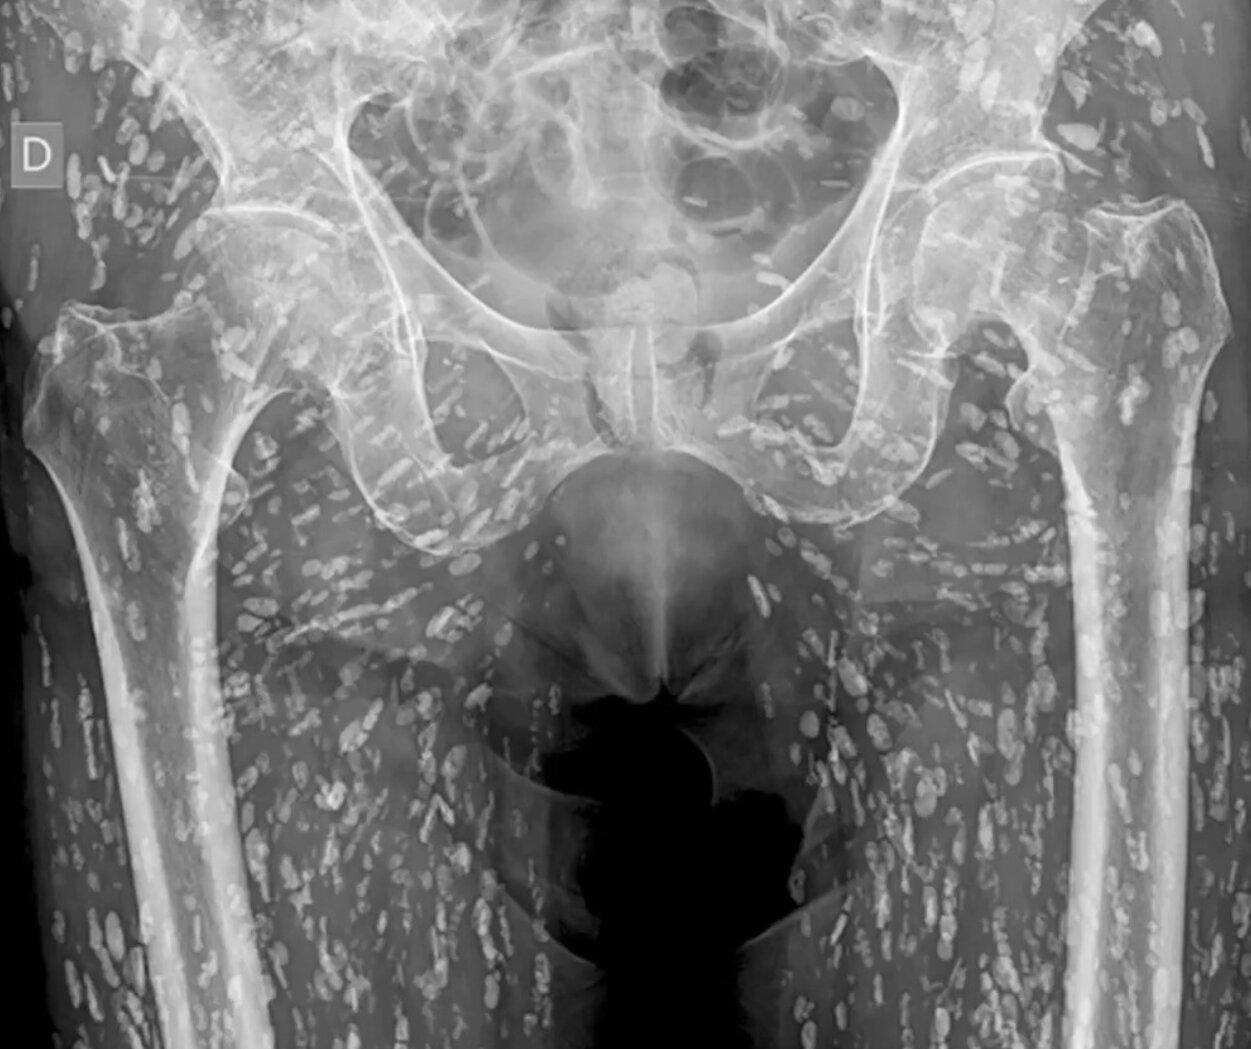

Một ca chụp X-quang tưởng chừng bình thường sau cú ngã lại bất ngờ hé lộ hàng trăm nang ký sinh đang trú ngụ khắp phần thân dưới của bệnh nhân. Điều gây sốc hơn cả là nguyên nhân đến từ một thói quen ăn uống phổ biến nhưng tiềm ẩn rủi ro lớn.

Một bức ảnh chụp X-quang kỳ dị, cho thấy cơ thể bệnh nhân chứa đầy nang sán dây đã trở thành chủ đề gây sốc trên mạng xã hội X (Twitter cũ), sau khi được bác sĩ cấp cứu Sam Ghali chia sẻ cùng lời cảnh báo: “Đây là một trong những phim X-quang điên rồ nhất mà tôi từng thấy.”

Trong hình ảnh, toàn bộ phần thân dưới của bệnh nhân, từ hông đến chân, xuất hiện chi chít những mảng trắng hình thoi như mưa đá bên trong cơ thể. Bác sĩ Ghali xác nhận đây là biểu hiện điển hình của bệnh ấu trùng sán dây heo, tên khoa học là cysticercosis, do loài ký sinh trùng Taenia solium gây ra.

“Cơ thể bệnh nhân này bị nhiễm đầy nang ấu trùng của sán dây heo, thứ mà chúng tôi thường gọi là ‘canxi hóa hạt gạo’ vì hình dạng đặc trưng trên X-quang,” bác sĩ Ghali giải thích.

“Đây là một trong những phim X-quang điên rồ nhất mà tôi từng thấy", bác sĩ Sam Ghali chia sẻ. (Ảnh: @EM_RESUS/X)

Ông cho biết bệnh nhân bị nhiễm sau khi ăn thịt heo sống hoặc chưa được nấu chín kỹ. Tuy nhiên, điều nguy hiểm không nằm ở việc ăn sán trực tiếp, mà ở việc nuốt phải trứng sán – thường qua đường phân-miệng, khi người nhiễm không rửa tay sạch sau khi đi vệ sinh hoặc sử dụng nguồn nước bị ô nhiễm.

“Vòng đời của sán bắt đầu khi một người ăn phải thịt heo chưa chín có chứa nang sán. Con sán trưởng thành phát triển trong ruột và đẻ trứng. Nếu trứng này truyền sang người khác qua tiếp xúc phân-miệng, người đó sẽ bị nhiễm cysticercosis,” Ghali giải thích thêm.

Ở bệnh nhân nói trên, các nang sán không xâm nhập vào não mà chỉ nằm ở phần mô mềm quanh hông và chân, nên không gây nguy hiểm tức thì. Trớ trêu thay, bức X-quang chỉ được chụp sau khi người này bị ngã và gãy xương, hoàn toàn không liên quan đến triệu chứng ký sinh trùng.

“Mặc dù nhìn rùng rợn, các nang sán ở phần cơ thường không gây biến chứng ngay. Nhưng nếu chúng di chuyển lên não, hậu quả có thể nghiêm trọng hơn nhiều,” bác sĩ cảnh báo.

Trong trường hợp ấu trùng di chuyển vào hệ thần kinh trung ương, người bệnh có thể mắc bệnh sán não (neurocysticercosis) , dẫn đến triệu chứng như đau đầu kéo dài, lú lẫn, động kinh và thậm chí tử vong nếu không điều trị.

Theo Tổ chức Y tế Thế giới (WHO), mỗi năm có khoảng 2,8 triệu người trên toàn cầu bị nhiễm sán dây heo, với số ca bệnh tập trung tại châu Á, Nam Mỹ và Đông Âu. Các chuyên gia y tế cảnh báo rằng tình trạng mất vệ sinh, thực phẩm kém an toàn và thói quen ăn thịt tái là nguyên nhân chính gây lây nhiễm.

“Lời khuyên của tôi là: hãy giữ vệ sinh tốt nhất có thể, luôn rửa tay sạch sẽ và tuyệt đối đừng ăn thịt heo sống hoặc chưa nấu chín,” bác sĩ Ghali nhấn mạnh trong phần kết thúc bài đăng.